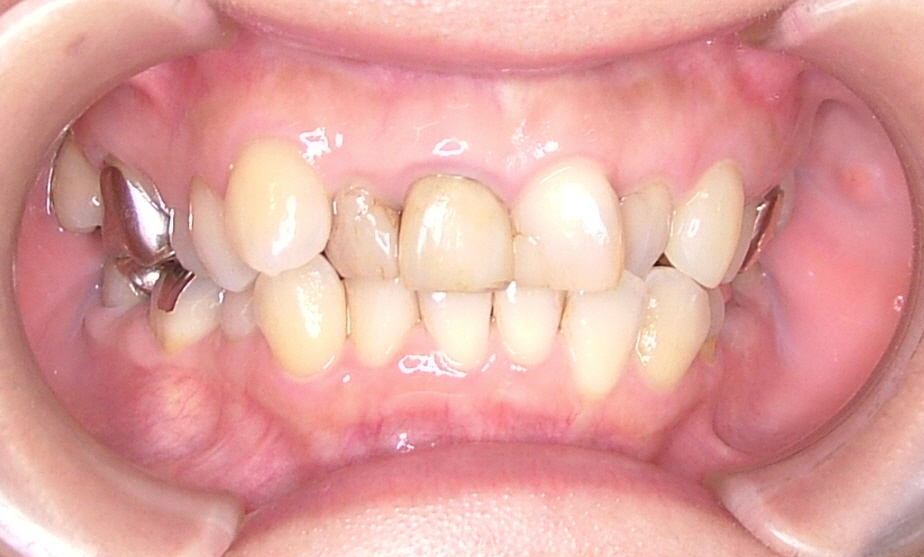

| 治療内容 | ジルコニアセラミック治療(上顎矯正後) |

|---|---|

| 治療期間・回数 | 13回(矯正含む) |

| 治療時の費用 | ジルコニアセラミック:484,000円 ※本症例当時の価格です。最新の費用はこちら |

| リスク・副作用 | 過度なブラシ圧をすると歯肉退縮する可能性があります。 |